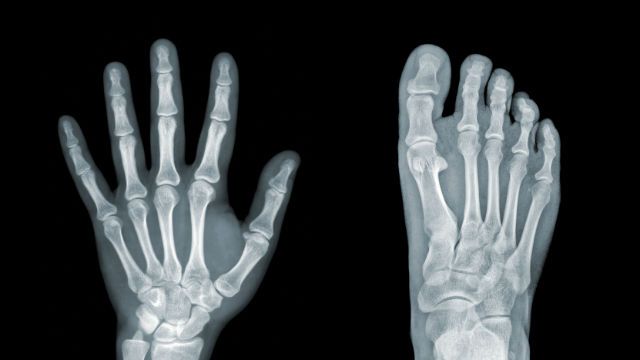

The term “bone fat” refers to the fat content of bone marrow, the tissue found within our bones. Bone marrow is home to a variety of cells, including blood and immune cells. It also has fat content, which can vary in concentration over time, and may be altered by lifestyle factors.

Dr. Styner notes that research has observed that more bone fat is produced by mesenchymal stem cells within the bone as a person ages, and it is hypothesized that this increased production of bone fat is a factor in older people’s susceptibility to bone fractures.

An earlier study, published in 2013 in the journal Radiology, analyzed the bone fat content of over 100 obese adults (between the ages of 19 and 45) with no other health issues, and found that the individuals with higher levels of muscle and liver fat also had higher levels of bone marrow fat. The researchers concluded that high levels of fat in the bone marrow increased an individual’s risk of bone fracture.

Lead author Dr. Miriam Bredella summarizes, “bone marrow fat makes bones weak. If you have a spine that’s filled with fat, it’s not going to be as strong.”